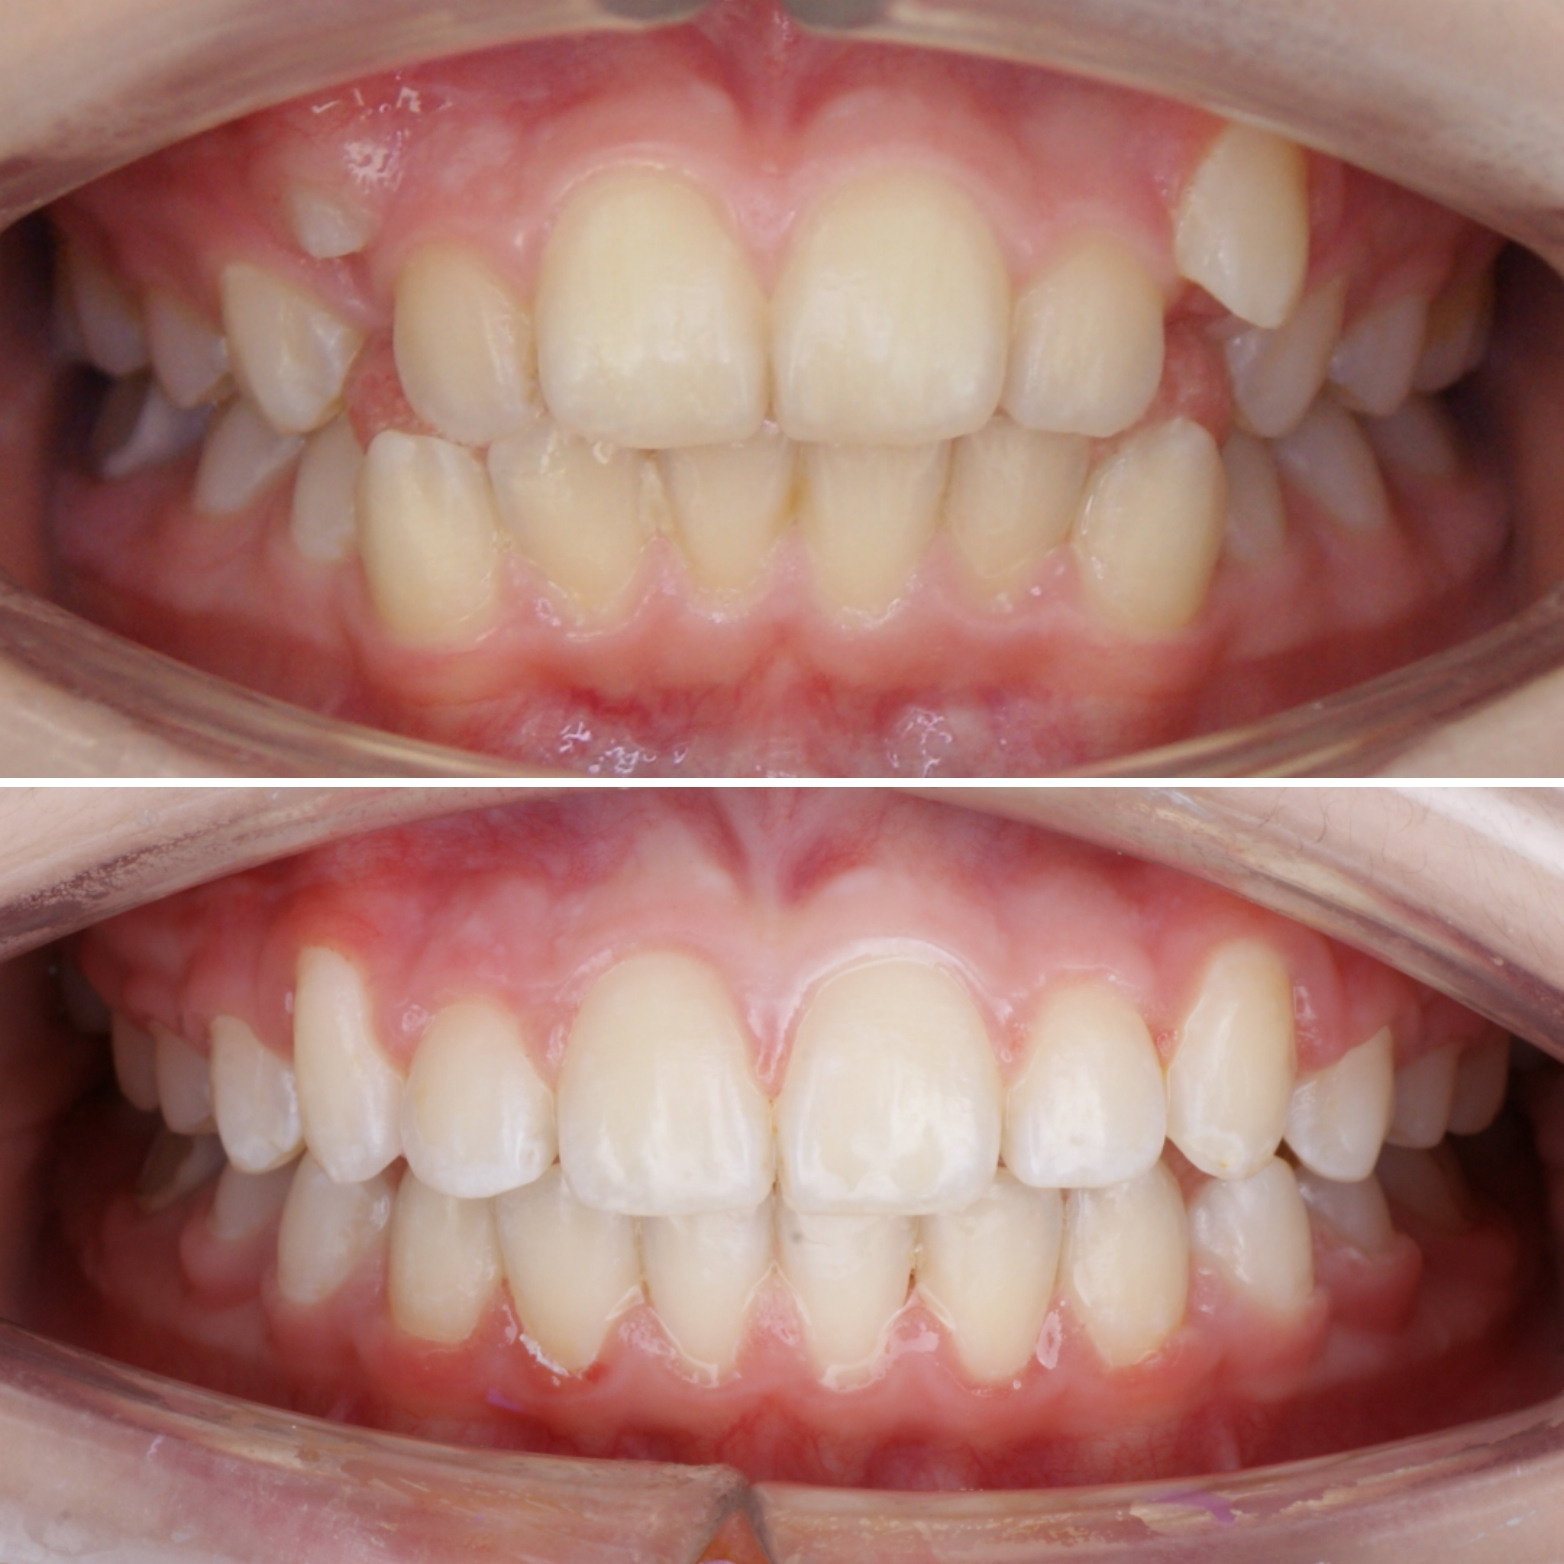

Большое путешествие зубов на своё законное место.

Эта фраза знакома многим ответственным родителям, которые привели на приём к ОРТОДОНТУ своего ребёнка в 5-10 лет, заподозрив проблему или понимая, что места постоянным зубам откровенно не хватает! Горькая правда в том, что брекеты - не волшебное средство от всех проблем, они "расставляют" зубы внутри сформированого объёма челюсти, но никак не влияют на её рост. Родители ждут, а тем временем драгоценное время, когда ребёнок растёт, уходит... Во взрослом возрасте приходится удалять здоровые зубы или прибегать к ортогнатической хирургической операции. 📸 На фото узкая нижняя челюсть, места постоянным зубам нет, боковые резцы прорезываются "вторым рядом".

✅ Помогаем с помощью расширяющей дуги, пружины и зацепных элементов, которые зафиксированы на МОЛОЧНЫЕ зубы

За 3 года (после завершения ортодонтического лечения) Вадим заметно подрос и возмужал😄, а главное, его угрюмое "Я не улыбаюсь" превратилось в широкую и яркую улыбку! Как быстро растут дети!😅